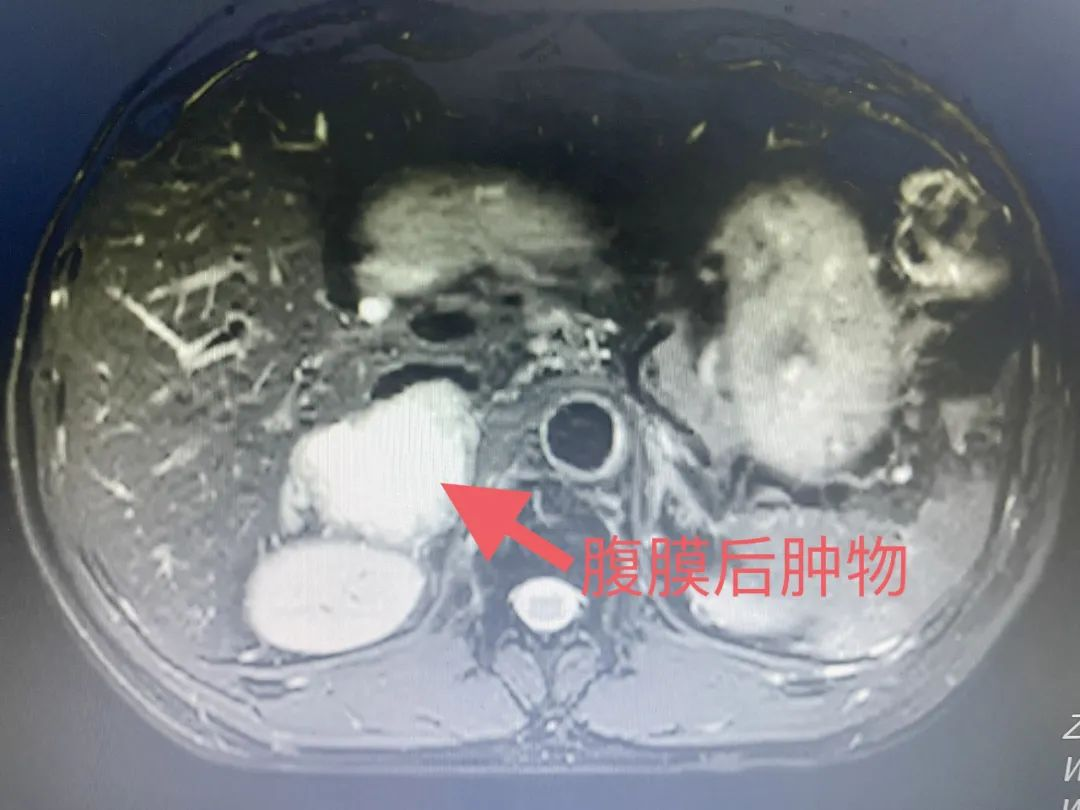

近日,年过五旬的吴先生体检发现右侧腹膜后肿物,听闻省医派驻专家毕学成主任医术精湛,患者慕名来到我院就诊。院前完善下腹部MRI增强扫描提示:右侧肾上腺区可见一团块状异常信号影,大小约50mmx45mmx46mm,T1WI呈等低信号,T2WI呈高信号,DWI边缘呈高信号,相应ADC呈低信号,增强扫描动脉期边缘实性成分轻度强化,临近下腔静脉明显受压偏移变扁。患者入院后进一步完善下腹部增强CT提示:腹膜后(下腔静脉后部-右肾上腺内侧区)可见一团块状密度影,大小约50mmx50mm。

▲下腹部MRI增强扫描提示右侧腹膜后巨大肿物